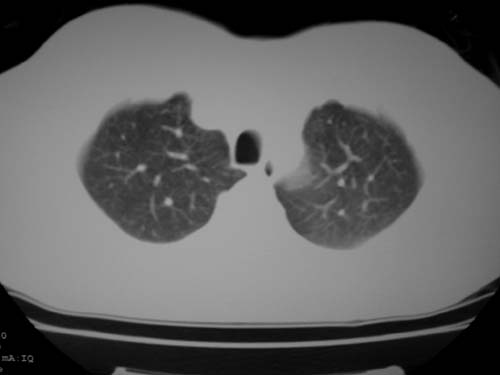

标题: CT19540: 31岁。自述结核性胸水治疗两个月后,在外院拍x线发 [打印本页]

标题: CT19540: 31岁。自述结核性胸水治疗两个月后,在外院拍x线发

右侧胸壁结节状软组织影伴相应肺叶内受侵,伴右侧胸腔积液。考虑:结核性可能大。

1、炎性病变,结核可能;2、右侧少量胸膜积液。

病灶也是发生于结核球好发部位,支持结核

右侧胸壁结节状软组织影伴相应肺叶内受侵,伴右侧胸腔积液,结合临床,首先考虑结核。

1)考虑右侧结核性胸膜结节。2)右侧胸膜增厚+包裹性胸腔积液。